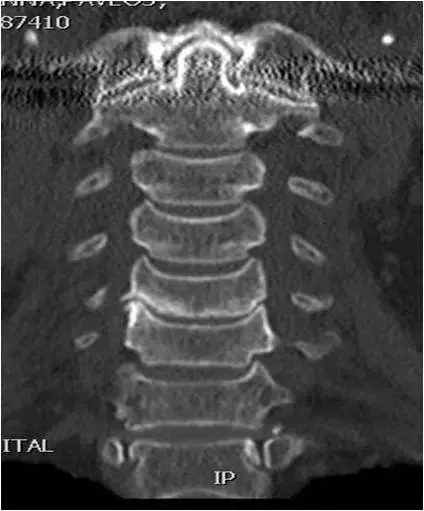

图16:颈椎CT扫描。冠状位重建。C5-C6关节间隙变窄,右C5-C6椎间钩突关节肥大,和C5椎体下终板硬化。